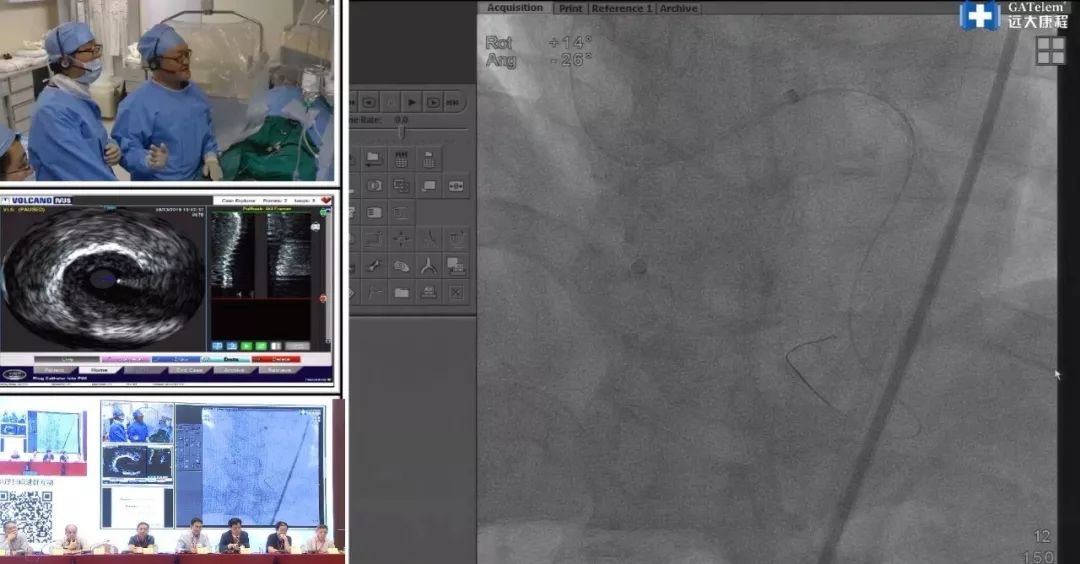

第二个病例由空军军医大学西京医院胡涛带来手术演示。该阶段由北部战区总医院荆全民教授、首都医科大学董鹏教授,首都医科大学附属北京安贞医院张宇晨教授,江门市中心医院彭宇程教授,南方医科大学珠江医院吴宏超教授,四川大学华西医院刘朝晖教授,广东省人民医院杨峻青教授,深圳市南山人民医院王执兵教授共同主持讨论。

该患者为60岁男性,曾心绞痛1年,患有高血压。造影结果显示该患者存在前降支,回旋支及右冠状动脉三支血管病变。此前进行两次手术,分别处理了患者的中间支及前降支,但前降支中段仍存在重度狭窄。右冠状动脉CTO存在明显残端,并伴有主动脉迂曲,后三叉前可能存在第二段CTO。右冠状动脉开口不好,远端后三叉存在病变,中间支较为粗大,但回旋支闭塞,前降支远端不理想,难度较大。但中间支上存在较好的间隔支,可作为逆向选择的侧支。专家组认为可考虑ADR技术,兼用IVUS指导右冠状动脉的选择。可选择较硬的逆向导丝穿过中间支侧支,进行Reverse-CART。

术中,胡教授选择右桡动脉和右股动脉首先进行正向开通CTO的尝试。失败后选择做逆向开通。然而前降支的支架及狭窄为逆向导丝的通过带来了极大的困难。在处理好前降支后,胡教授选择从第一间隔支进行穿刺。双侧造影结果显示,该段完全闭塞,硬导丝均难以通过,考虑到近端及远端均为闭塞段,逆向导丝进入真腔较难,故再次选用正向做ADR。由于硬斑块的存在,选用Gaia 3穿过。 后遇到较为迂曲的部位,微导管无法通过,稍使用Knuckle 技术以增强支撑力,接着采用Corsair微导管进行扩张、pilot 200进行正向开通,最终通过双腔微导管成功植入3枚支架。

专家组表示,该病例从早上持续到下午,术者在手术过程中不断地遇到困难并解决困难,不断地根据患者的情况灵活选择术式,这是让术者不断成长的关键,也正是CTO的魅力所在。